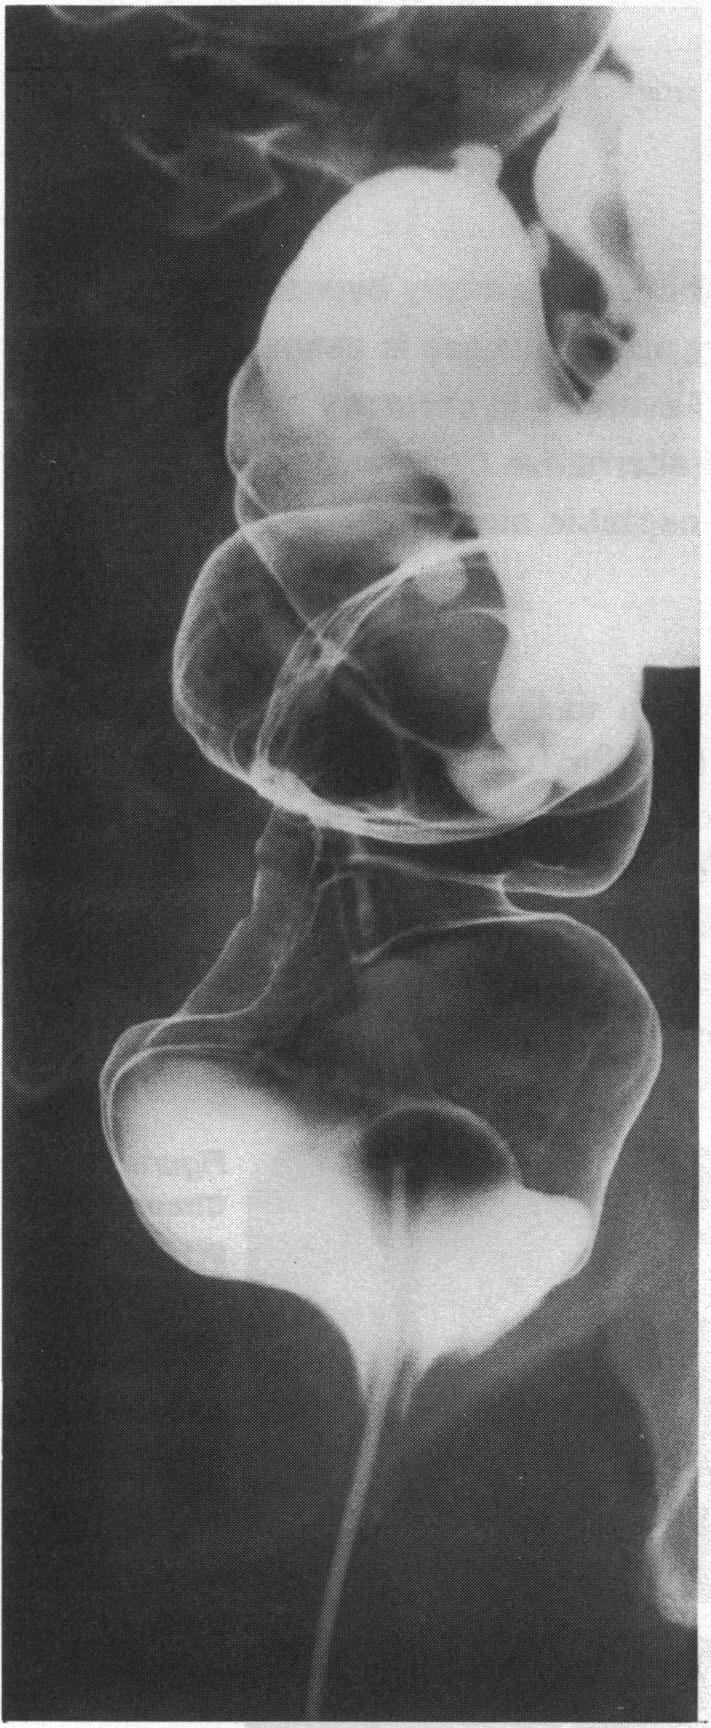

Systemic amyloidosis results in diffuse deposition of amyloid proteins in various organs. Localized deposits in the form of nodules also occur but are rare in the gastrointestinal tract. A localized amyloid deposit in the rectum that was clinically indistinguishable from carcinoma of the rectum or prostate is described.

系统性淀粉样变性导致淀粉样蛋白在各个器官中弥漫性沉积。以结节形式出现的局部沉积物也会发生,但在胃肠道中较为罕见。本文描述了一例直肠局部淀粉样沉积物,其在临床上与直肠癌或前列腺癌无法区分。